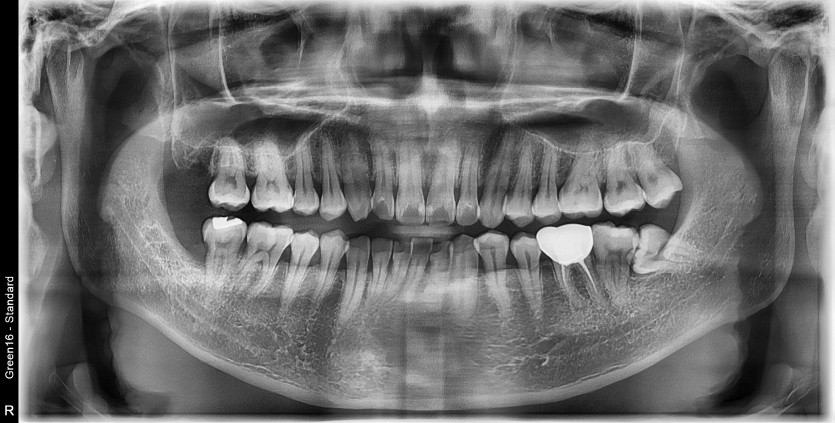

#18,28,38,48 사랑니 발치

구강 외과 전문의가 당일 발치했습니다.